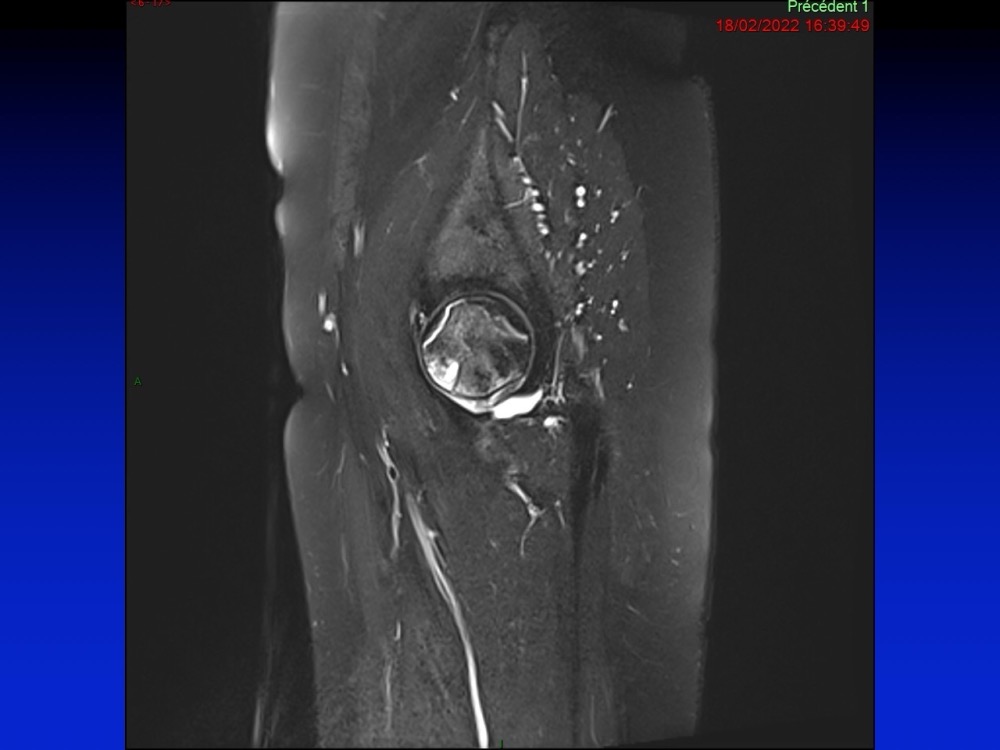

Aboudaram / Burns 11/01/2023